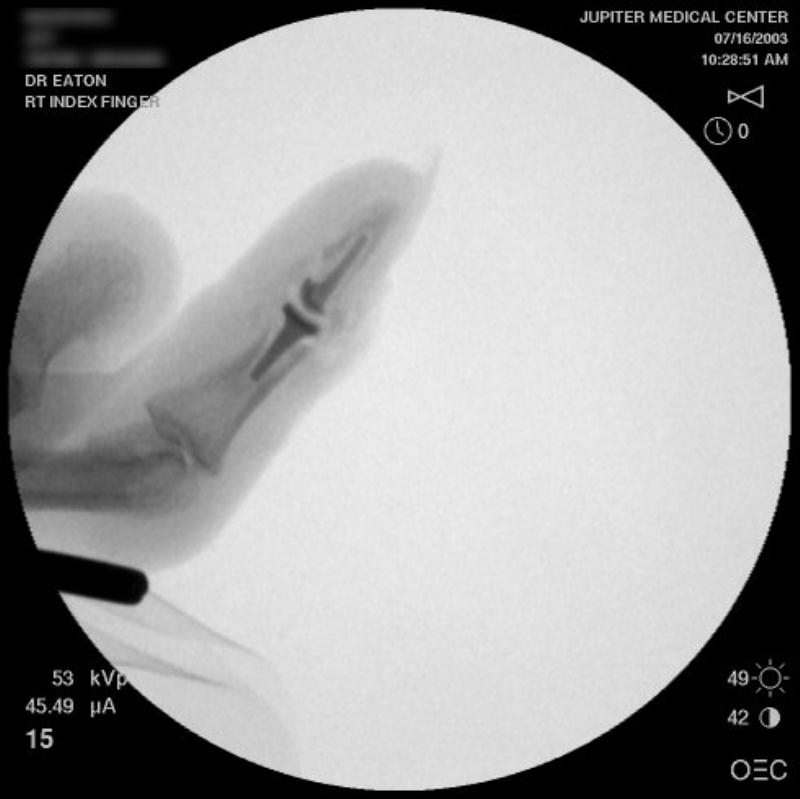

Intraoperative fluoroscopy.

The trial implant sizer shows the true size of the implant. The final implant has a radiolucent coating  which makes it appear smaller than it is on Xray.

Final implant radiographs.